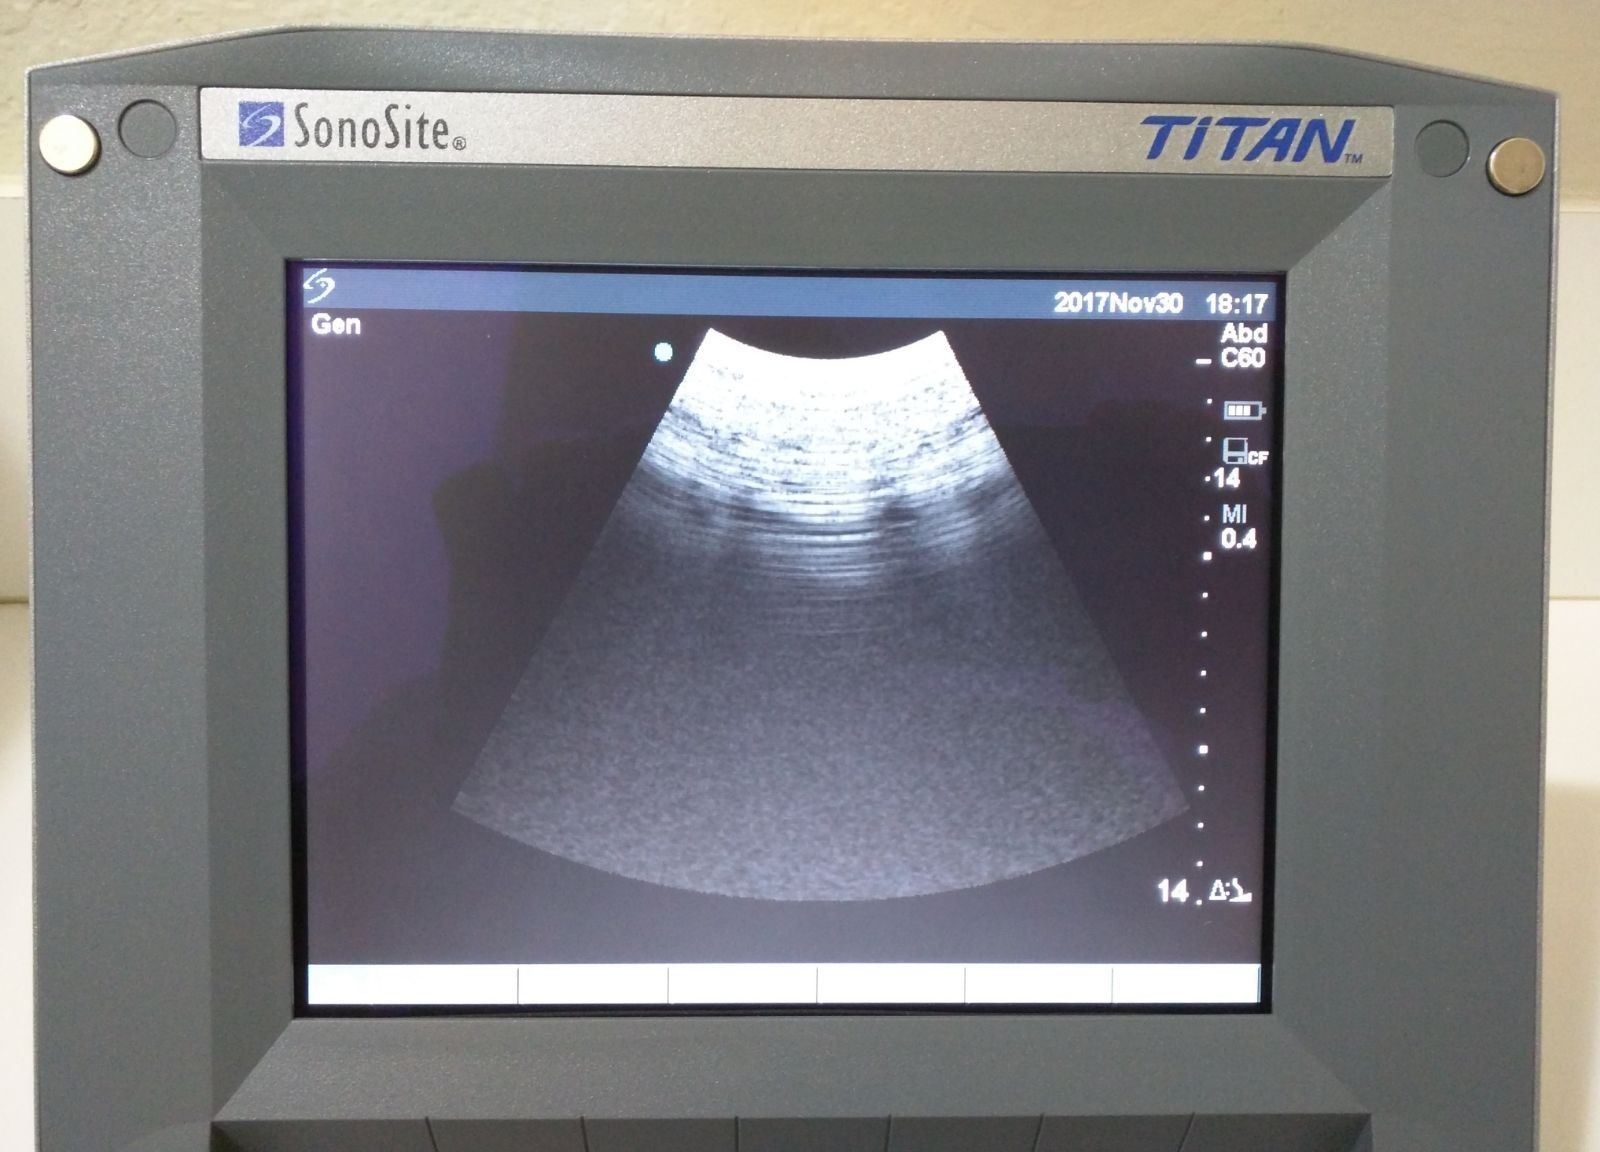

Exceptional Imaging Quality

The SONOSITE TITAN OB/GYN ultrasound offers state-of-the-art imaging technology. This device uses advanced algorithms to provide clear, high-resolution images. It includes two probes: a 1-C60 convex and a 1-ICT transvaginal probe, ensuring versatility in different obstetric and gynecological applications. Because of its compact design, the SONOSITE TITAN is perfect for both hospital and remote settings, making it an ideal choice for healthcare providers.